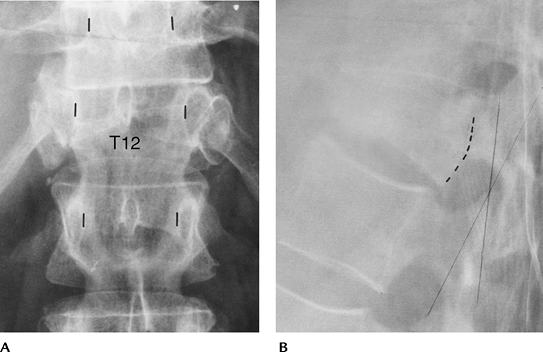

![]() |

FIGURE 3-26 (A)

Lateral radiographs demonstrating the three columns proposed by Denis. Anterior-anterior longitudinal ligament, anterior disc, and vertebral body. Middle-posterior disc, body, and posterior longitudinal ligament. Posterior-facet joints, ligamentum flavum, interspinous, and supraspinous ligaments. (B) Lateral radiograph shows mild compression of L1 (arrow) with splitting of the neural arch (curved arrow) caused by hyperflexion distraction injury. Unstable with three-column involvement. |